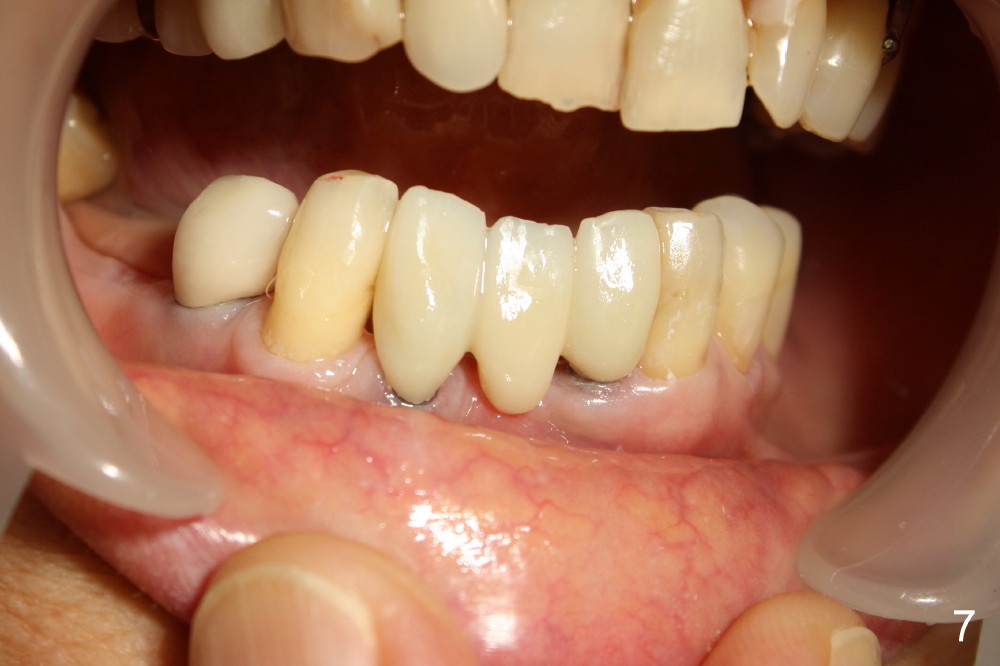

Two of one piece implants (3x17 mm) were placed at the sites of #23 and 26 on February 13, 2013 (Fig.5). The implant at the site of #26 was placed a little too labially with possible coronal labial plate fracture. Immediately fabricated was a provisional FPD, which was replaced by a definitive one three months and a half later (Fig.7).  PA in Fig.6 is taken five months post implantation (I: one-piece implant).